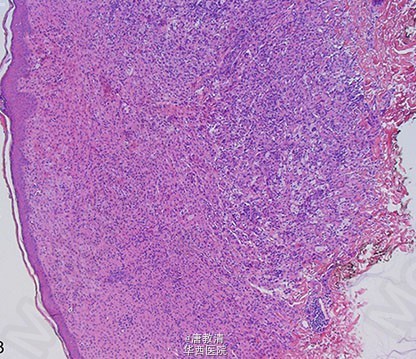

播散性黄瘤——可不单单是皮肤问题

一个24岁的白人女性,躯干和腋窝呈现边界清楚的红褐色丘疹和结节约两年。值得注意的是,患者在这些皮肤病变发现之前接受了扩大切除蝶鞍肿块。入院前,患者有视野缺损,体重增加及尿崩症。